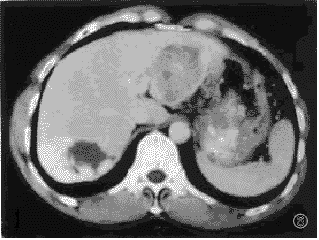

2.2.2 肝血管瘤合并肝癌多期连续扫描表现:在2例肝血管瘤合并肝癌病例,肝癌病灶数共2个,直径分别为2.5cm,4.5cm,在30秒增强时,两者表现为不均匀强化,60秒,2分钟,5分钟,10分钟,15分钟表现为低密度灶,密度欠均匀。血管瘤病灶共7个,1例为3个血管瘤合并1个肝癌病灶,另1例为4个血管瘤合并单个肝癌病灶,其中血管瘤病灶则表现为典型血管瘤强化特征。(见图5,6)。

, http://www.100md.com

图5 30秒扫描,左外叶肝癌病灶,呈不均匀强化,右的叶肝血管瘤病灶呈周围结节状强化;

图6 60秒动态扫描.肝癌病灶呈不均匀低密度区,右后叶血管瘤病灶强化向中心扩展